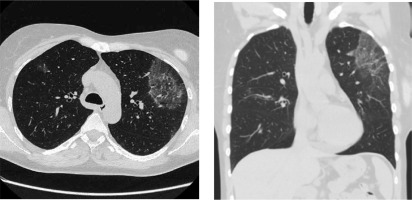

In December 2019 the patient was admitted to the Department of Rheumatology and Immunology due to exertional dyspnea and cough. Physical examination revealed diffuse expiratory wheezing and prolonged expiration. Initial workup revealed blood eosinophilia (2840 cells/µl) and an elevated level of immunoglobulin E (134 IU/ml, reference range < 100); with normal levels of vitamin B12, tryptase and immunoglobulin G. There were no parasitic eggs or larvae in a stool sample. The patient was negative for FIP1L1-PDGFRA, JAK2 and ETV6-PDGFRB mutations. A bone marrow aspirate revealed an elevated level of eosinophils (< 10% of the cells); no other pathologies were identified. Cytogenetic analysis showed a normal female karyotype. Ground glass opacities on high-resolution CT were described (Fig. 2). Bacterial and fungal cultures of BAL fluid did not yield any organisms. Increased eosinophils in BAL fluid (10%) confirmed HES flare. Therapy with intravenous methylprednisolone (40 mg daily for 5 days, subsequently tapered), combined with inhaled GC and bronchodilators was started. Reduction of methylprednisolone dose less than 32 mg daily led to HES flare.

Off-label treatment with benralizumab (30 mg s.c. every 4-6 weeks) 20.03.2020 was started, resulting in significant improvement of respiratory signs and symptoms, normalization of eosinophil count and reduction of methylprednisolone dose to 3 mg daily (after 5 doses of benralizumab administration). No substantial side effects have been noted during treatment and 6-month follow-up.